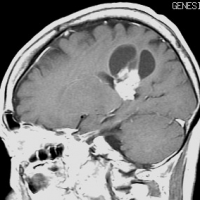

高齢者の無症候例です

60代の女性に無症候で発見された稀な部位のPXA。結節様ですが脳とのはっきりした境はなく,多房性ののう胞を伴っていました。T2とFLAIR像ではわずかな浸潤像あるいは腫瘍周辺浮腫が疑われます。PXAに特徴的な画像ですが,大脳深部発生でもあり,PXAと画像診断することはできません。定位脳生検術 MRI-guided sterotactic biopsyで病理組織診断を行ない経過観察しました。

3年観察したら嚢胞を伴って増大しました。幸いのう胞性拡大が脳表方向であったのでparietal transcortical approachで全摘出できました。側脳室三角部腫瘍への到達法と同じアプローチですが,この経路では頭頂葉症候を後遺することがありません。

術後は無症状で8年間再発はありません。